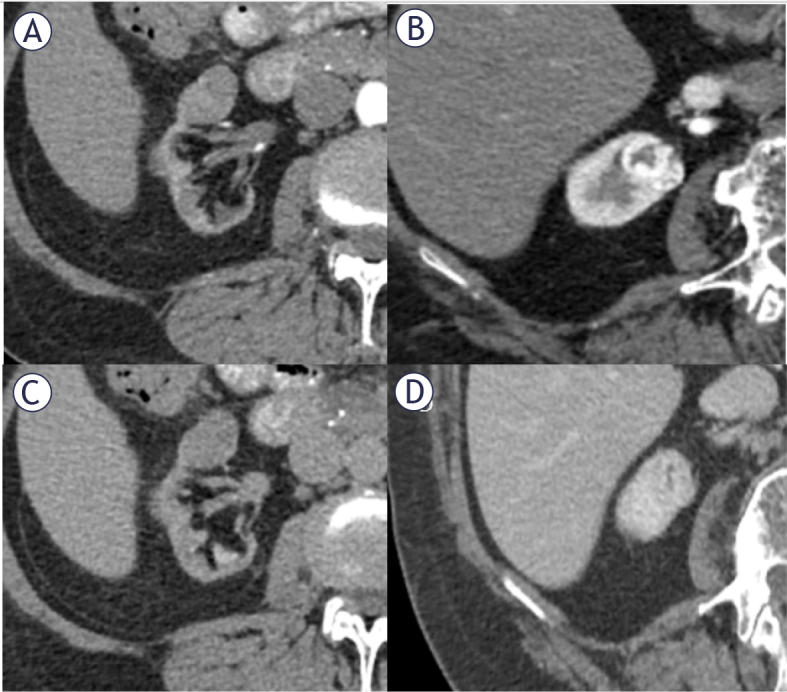

Background: The incidental detection of indeterminate small renal masses (SRMs) has been rising continuously over the last few decades. The aim of our study was to assess selected contrast enhanced computed tomography (CECT) parameters in the characterization of indeterminate SRMs and compare them with selected magnetic resonance imaging (MRI) data.

Patients and methods: Patients with indeterminate SRMs discovered on CECT were included in the study. Selected CECT features have been analyzed as differentiating between clear cell renal cell carcinoma (ccRCC) and other etiologies of SRMs. In 82% of patients, which had available MRI data, a comparison between selected MRI and CECT parameters were performed.

Results: Relative washout in CECT had the best accuracy (76.5%), sensitivity (88.9%), as well as satisfactory specificity (69.7%) in ccRCC prediction. The cut-off point determined in receiver operating analysis using the Youden index for this parameter was 11.54. Multivariable analysis showed that only T1 SI ratio < 0.73 from MRI parameters and relative washout > 11.5 from CECT parameters were independent predictors of ccRCC (OR: 30.86, 95% CI: 1.58-600.26, p = 0.024; OR: 15.36, 95% CI: 1.52-155.16, p = 0.021).

Conclusions: In clinical practice, the use of both CECT and MRI indicators, especially T1 SI ratio < 0.73 for MRI and relative washout > 11.5 for CECT, can support physicians in diagnosing and treating patients effectively.